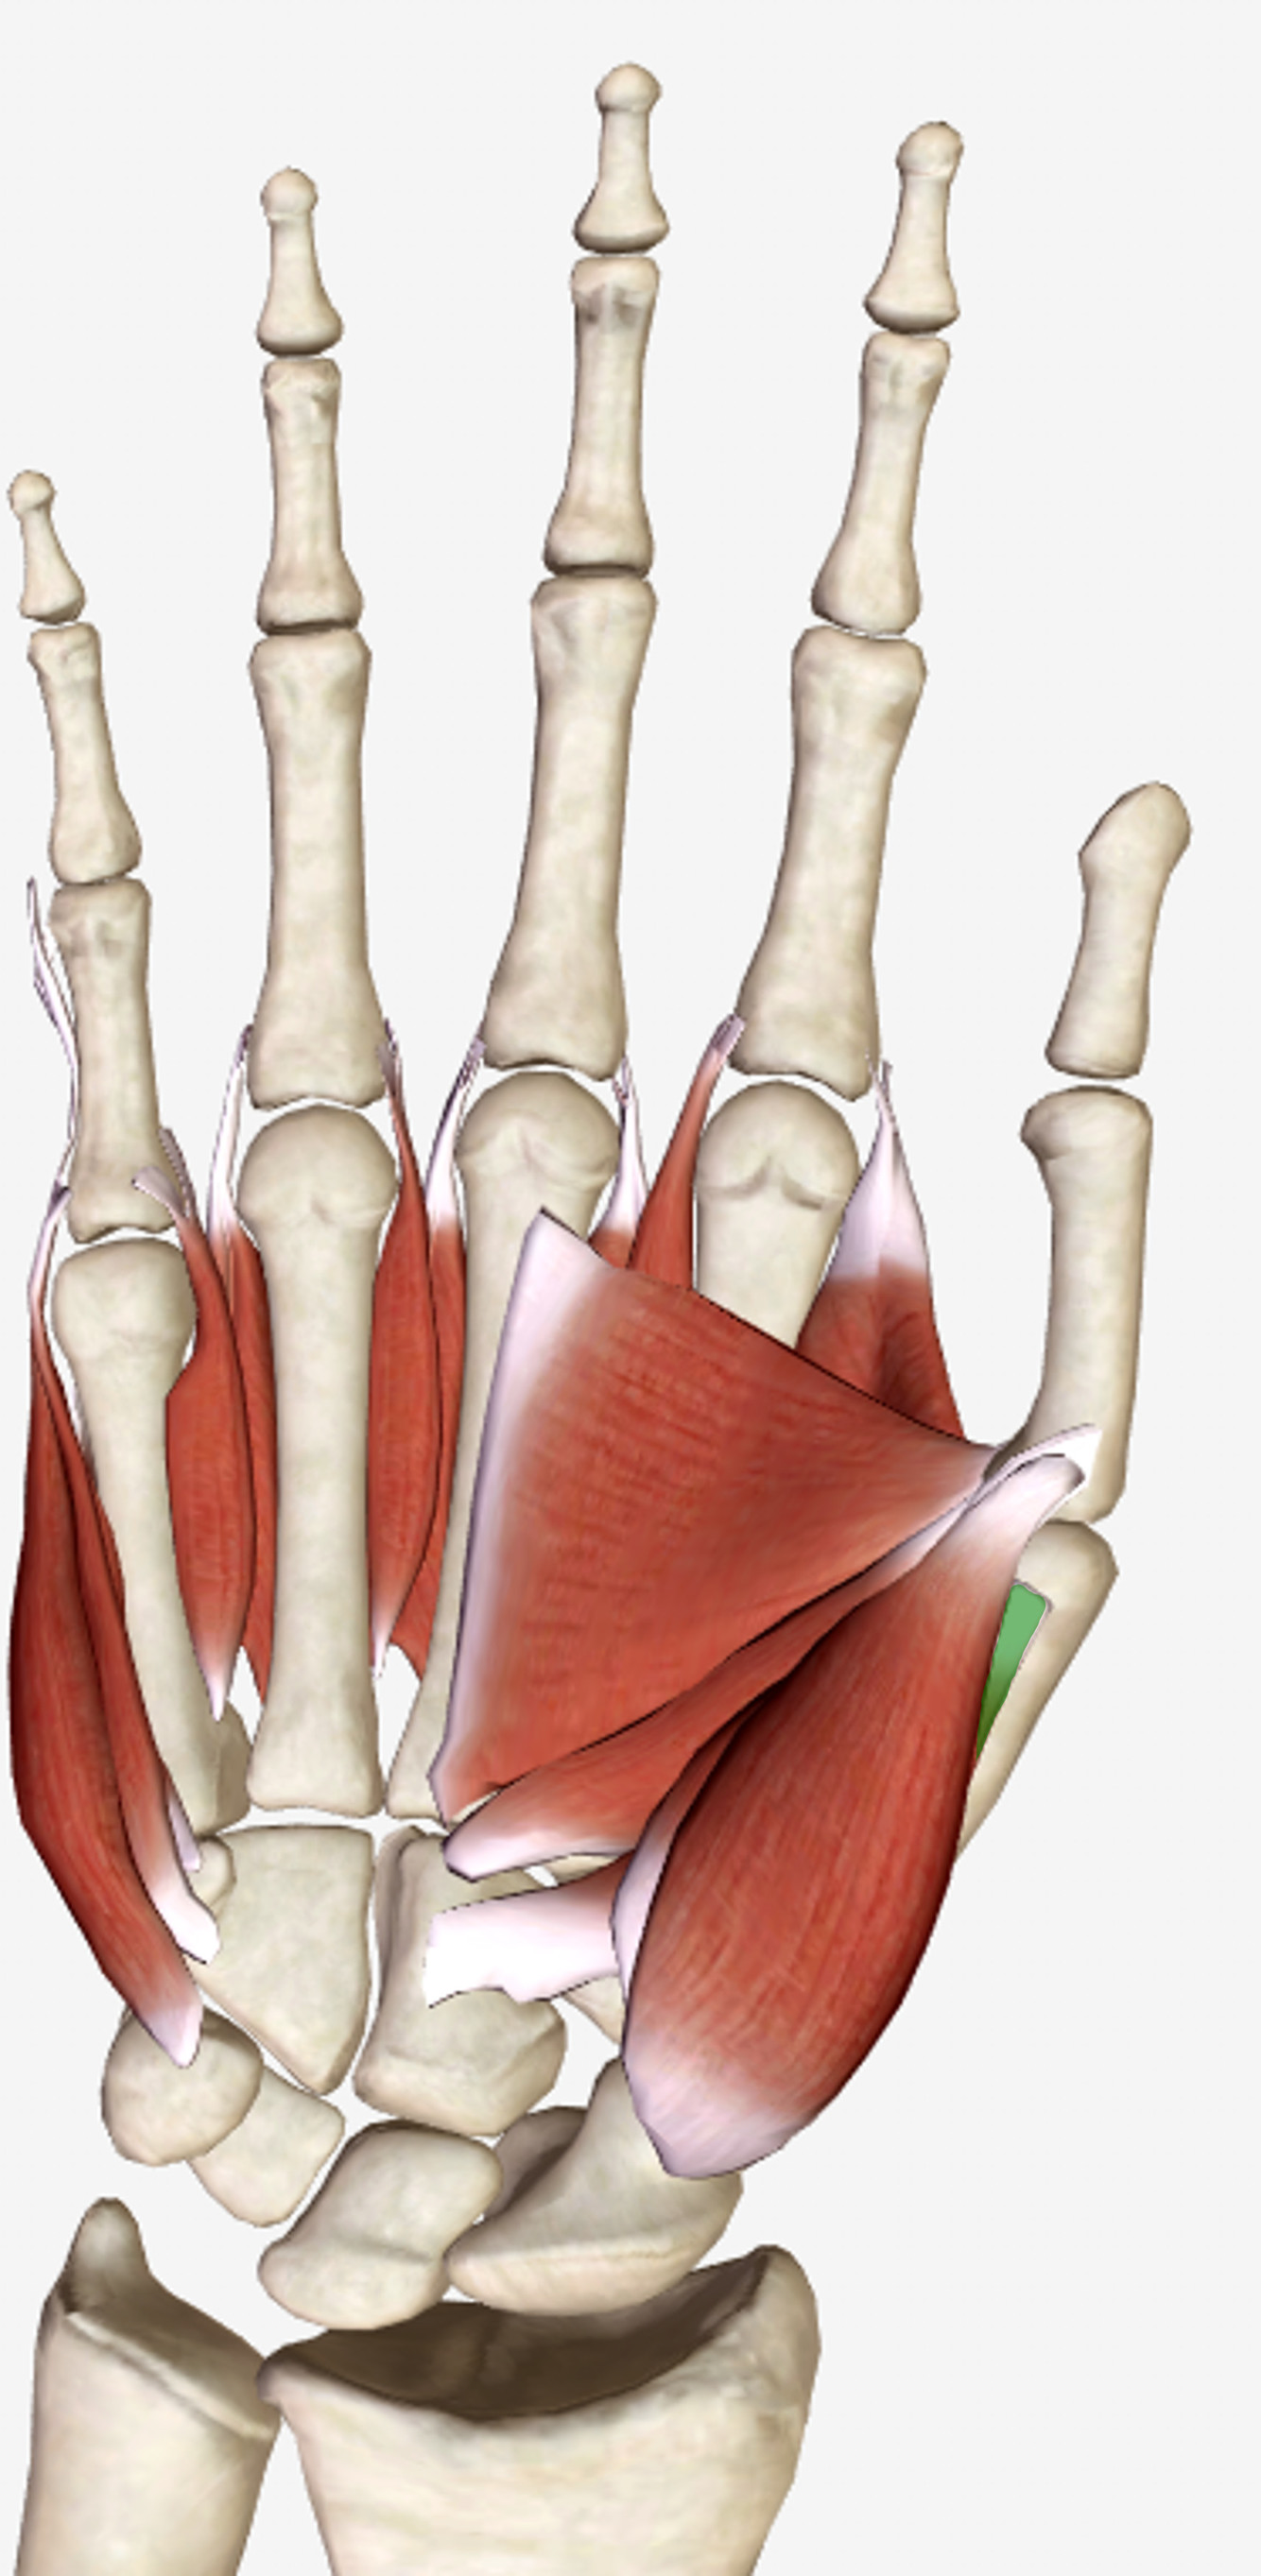

What is the innervation of this muscle?

Muscle - Flexor pollicus brevis

Median nerve